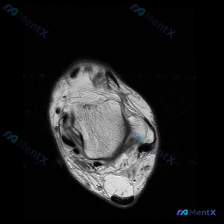

看到这份踝关节MRI的读片申请,核心问题是排查软骨异常,整理了完整的读片和分析思路分享给大家。 一、影像基本信息 这是一张踝关节MRI轴位T2加权图像,扫描层面为踝关节水平,展示胫骨远端后方、距骨及后踝周围软组织结构: 1. 骨结构:胫骨后缘、距骨体后部轮廓清晰,骨皮质低信号、骨髓中等信号,未见明显...